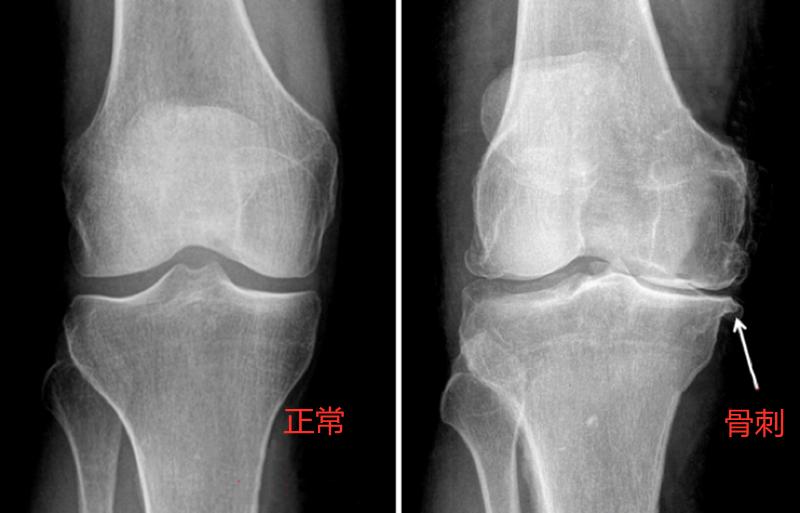

骨刺其实不是“刺”,大部分骨刺是圆形块状的,表面光滑,更像个硬疙瘩,它一般不会“扎”关节,许多骨刺是无症状的,也不会疼,除非通过膝盖X光检查,否则患者不知道自己长了骨刺。然而比较大的骨刺可能会压迫周围的软组织,引起的症状包括膝盖疼痛,麻木,僵硬,关节处摸起来不平,活动范围减小以及肌腱炎。

骨刺是骨关节炎的征兆之一,骨刺的影响包括早晨醒来膝盖僵硬肿胀,肿胀分软肿胀和硬肿胀,软肿胀意味着膝盖里有积液,硬肿胀则是长了骨刺的表现。另外骨刺会在膝关节里制造噪音,健康的软骨表面比冰面还光滑,摩擦时没有声音,当软骨磨损或者遭到损坏时,表面出现粗糙的骨刺,行走时发出噪音。